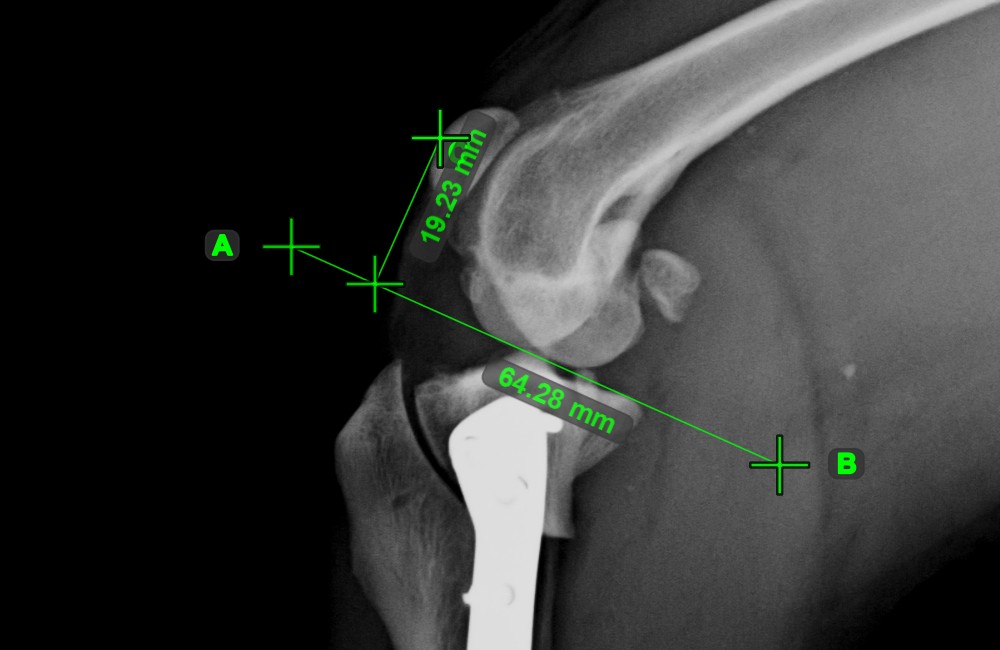

Vonal létrehozása¶

Válassza ki a Vonal létrehozása eszközt, és rendelje hozzá az egyik elérhető egérgombhoz. Helyezze el a kezdő- és végpontot a jelenetben, vagy válassza ki őket a már meglévő pontok közül a képen. A két pont közötti távolság automatikusan kiszámításra kerül az alapértelmezett kalibrációs adatok, vagy a hosszkalibráció mérés által újrakalibrált adatok alapján.

Módosítsa a kezdő- és végpontot az Elem kiválasztása/mozgatása eszközzel. A két pont közötti távolság automatikusan újraszámításra kerül.